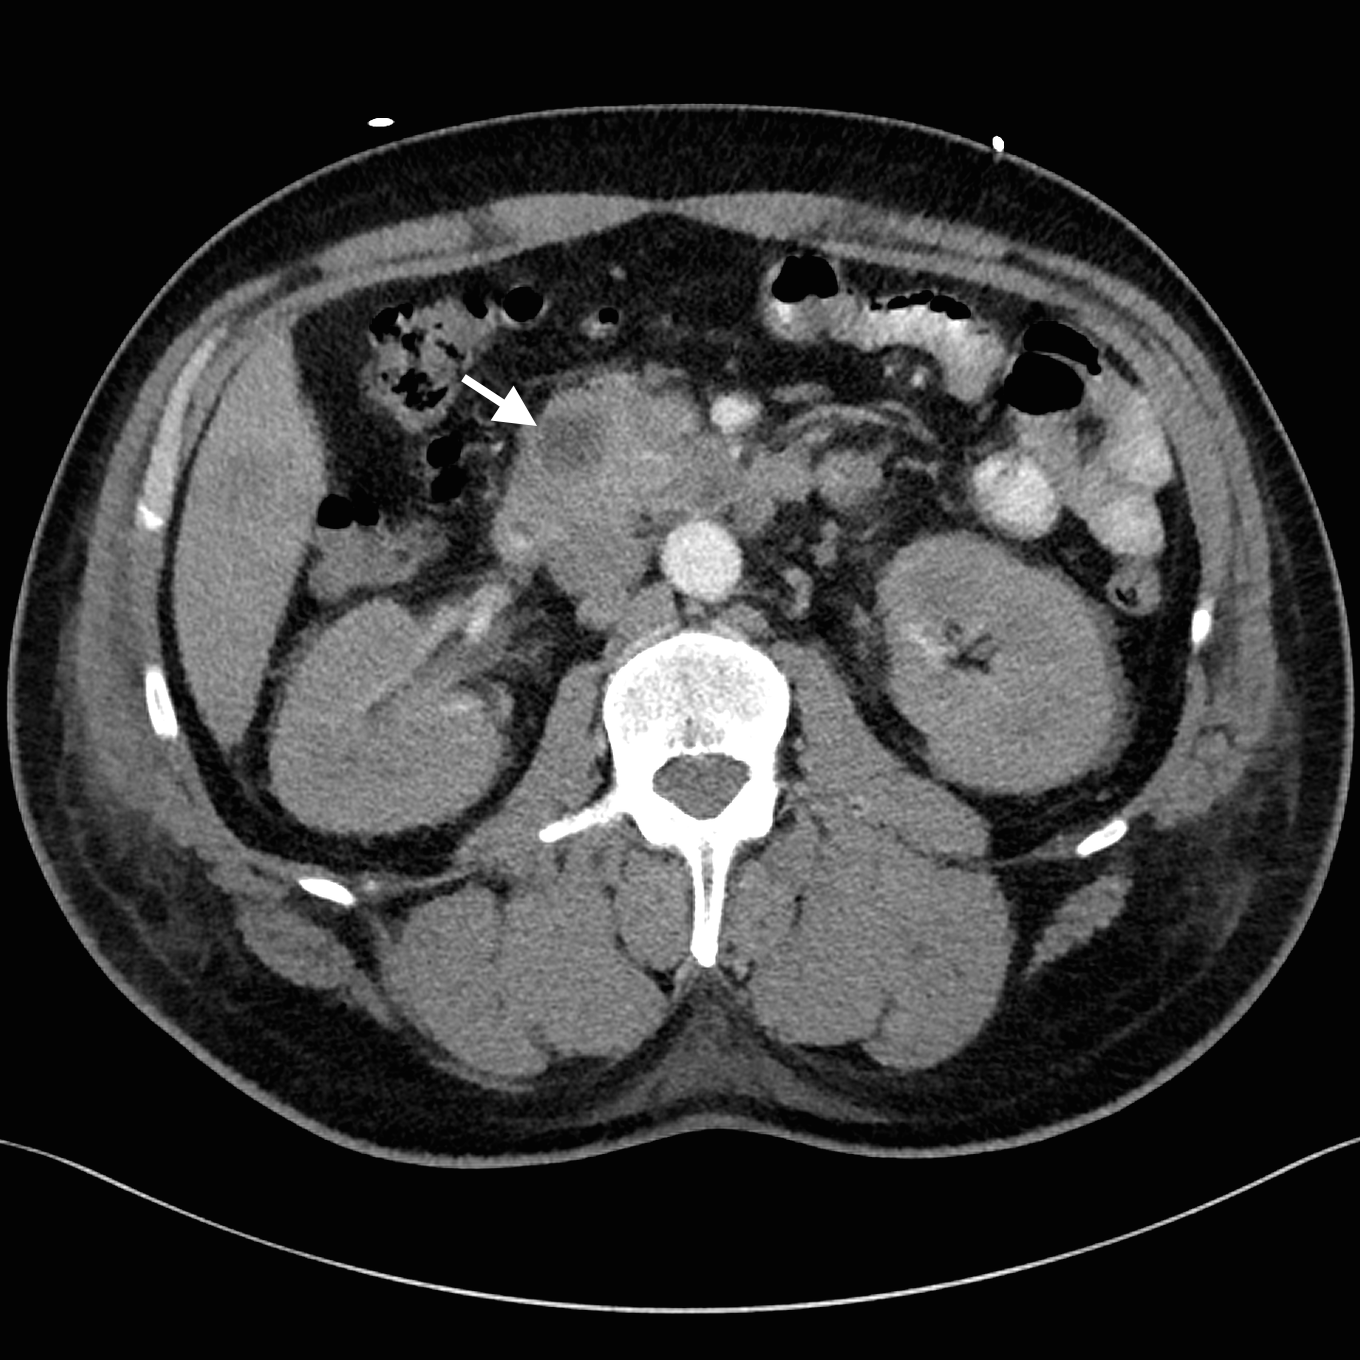

Despite adequate fluid replacement, the patient remained oliguric and developed deteriorating uraemia, so that haemodialysis was initiated. This facilitated further investigation with contrast-enhanced triple-phase hepatic CT, which confirmed a 25 × 23 × 17 mm heterogeneous head of pancreas mass, together with multiple hypodense liver lesions (Figure). Ultrasound-guided fine-needle aspiration biopsy of a liver lesion was performed. The cytological profile and immunohistochemical characteristics of the biopsy sample were consistent with metastatic adenocarcinoma, probably of pancreatic origin.